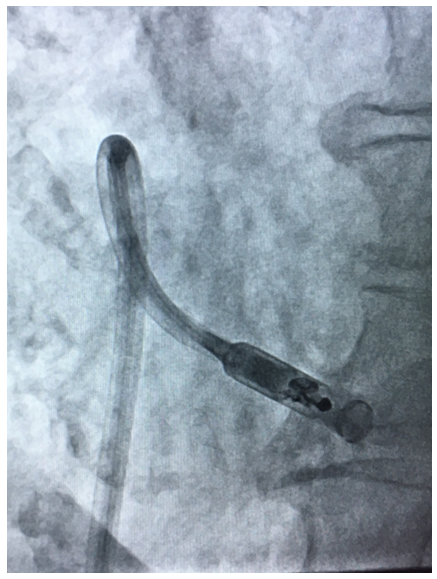

The Micra Leadless pacemaker is a miniaturised, single chamber pacemaker system – this means it is designed to pace only within the right ventricle of the heart. It is 93% smaller than traditional pacemakers.2 It is delivered via a catheter (a long plastic tube) inserted through the femoral vein at the top of the right leg and implanted directly inside the right ventricle of the heart (see figure). The Micra device eliminates the need for a separate large battery, a device pocket and insertion of a pacing lead, thereby potentially preventing many of the complications associated with traditional pacing implants but providing the same benefits.

The Micra is a self-contained pacemaker, which has 4 nitinol (memory metal) wires at its tip, which help secure the device to the heart muscle and prevent it from moving subsequently. It is introduced through a large sheath inserted at the top of the right leg. The sheath has a flexible tip helping to steer the catheter to the correct position in the right ventricle (see figures). Despite the differences in size and shape, the Micra device is very similar to standard pacemakers in regards to functionality and features and, by design, is inherently MRI-conditionally safe.